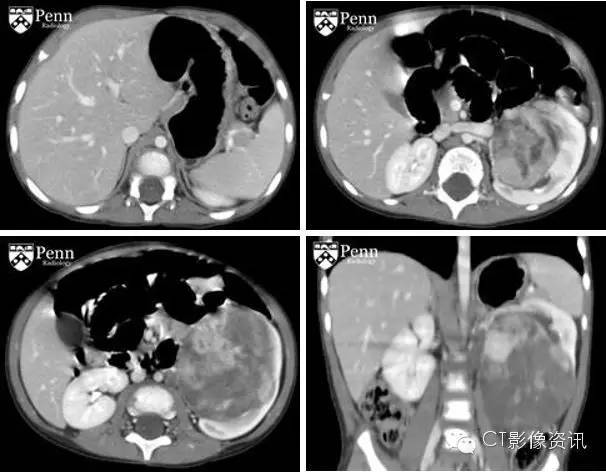

检查结果 从腹部增强CT的轴位及冠状位上可以看见一个较大、边界清晰的肿块从左肾的髓质发出并向上影响到邻近的肾实质。此肿块表现出不均匀强化,成分混杂,包括低密度灶、坏死以及囊变。从左上图可见左肾上腺外观正常未有病变。左下图可见低密度的左主动脉旁淋巴结以及相应的淋巴结转移。对侧肾脏未见肿块。

最终诊断:肾透明细胞肉瘤(CCSK)